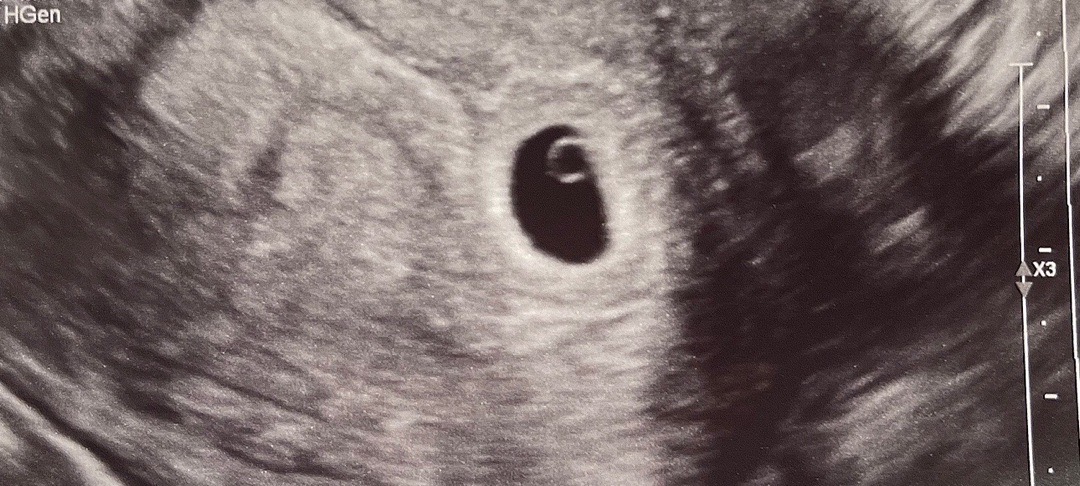

5주2일차 아기집 난황까지 확인했어요 :)

기적처럼 자임 성공후(실은 임신인지 몰라서 이것저것 다 한 산모…) 병원 갈때만 기다렸는데요~ 나이도 많고 임신중독증 초고위험 임신이라 다니던 대학병원으로 첫 검진 갔어요! 역시 교수님은 아기집이나 난황에 대해선 문제 없으니 별 말씀 없으시고 쏘쿨 -ㅋㅋㅋ 그것보다 앞으로 임신 유지에 대해서만 더 신경쓰시더라고요! 아스피린까지 처방받았어요 ㅎㅎㅎㅎㅎ 앞으론 서브 병원도 같이 격차 방문 예정이예요:) 다이아 반지까지 봐서 기분이 째지네요 👶🏻💍 다들 행복한 임신 생활 되길 바래요 !!